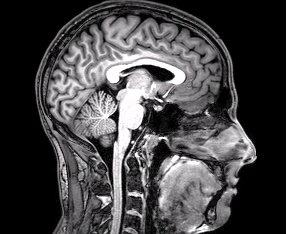

Medical treatment cannot prevent brain injuries from occurring in the first place, but it can prevent brain injuries from becoming worse. Many patients fail to seek medical attention after suffering a brain injury, and this cavalier response may lead to serious health risks. Deciding not to seek medical attention may also make it more difficult to prove the cause and extent of the brain injury, which can become an issue if patients decide to file personal injury lawsuits to seek compensation for their brain injuries, for example. Speak with Schauermann Thayer to learn more about whether your situation may be appropriate for legal compensation.

There have been numerous cases in which brain injury patients have suffered brain bleeds, hematomas, and other issues without fully realizing the extent of their own ailments. These patients may suffer unexpected deaths due to the effects of initially unrecognized or underestimated brain injuries. Even if patients are under the impression that they have suffered a relatively light knock to the head, it is imperative that they seek medical attention from a qualified healthcare professional as soon as possible. Early intervention and testing can spot serious issues before they become worse. Tests such as MRIs can detect the presence of potentially life-threatening issues, such as hematomas.